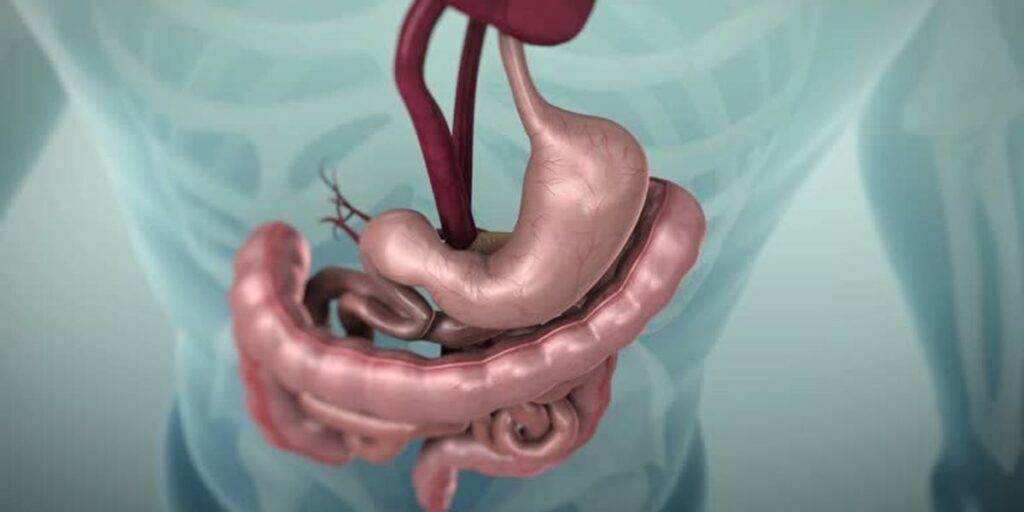

Peristaltika është lëvizja automatike, ritmike dhe valore e muskujve që veshin traktin tretës. Ky proces mundëson kalimin e ushqimit nëpër sistemin e tretjes: fillon në fyt gjatë gëlltitjes dhe vazhdon në ezofag, stomak dhe zorrë.

Trakti tretës funksionon si një tub i gjatë i përbërë nga organe të lidhura mes tyre. Muret e tij përmbajnë muskuj dhe nerva që reagojnë sapo futet ushqimi ose lëngu. Këto tkurrje ritmike e shtyjnë përmbajtjen përpara deri në nxjerrjen e saj.

Ajo ndodh përgjatë gjithë traktit tretës, sidomos në ezofag. Procesi nis në fyt dhe vazhdon drejt stomakut. Në ezofag ka dy valë kryesore: valën primare, që nis me gëlltitjen dhe valën sekondare, që aktivizohet nëse e para nuk mjafton

Më pas vazhdon në stomak dhe zorrë, ku ritmi ngadalësohet për të lejuar përzierjen dhe përthithjen.